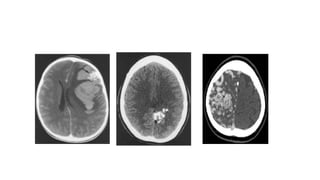

• CT

Normal, if AVM is very small

Iso/hyperdense serpentine vessels

Calcification in 25-30%

AVM bleed = IPH/IVH/SAH

Post-embolization – embolics appear hyperdense within nidus

• CECT

Strong enhancement of arterial feeders, nidus and drainingveins, giving

appearance of “bag of worms”

• CTA

Depicts enlarged arteries, draining veins

• #23 Showing avm with parenchymal bleed 3. Cect showing baf of wroms appearance